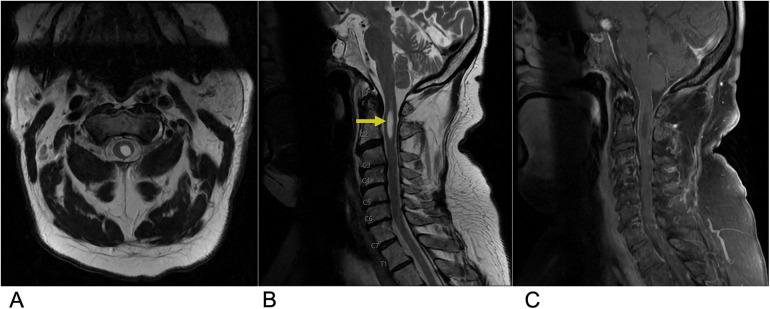

Spinal lesions encompass a diverse range of pathologies, including primary and secondary tumors, infectious processes, vascular malformations, traumatic injuries, and degenerative conditions, each with distinct imaging characteristics crucial for accurate diagnosis and management. Imaging plays vital roles in assessing lesion morphology, anatomical localization, and neurological impact, guiding clinical decision-making and therapeutic planning. This review systematically explores spinal lesions based on their anatomical compartments, highlighting key radiological features and providing a comprehensive reference for radiologists.